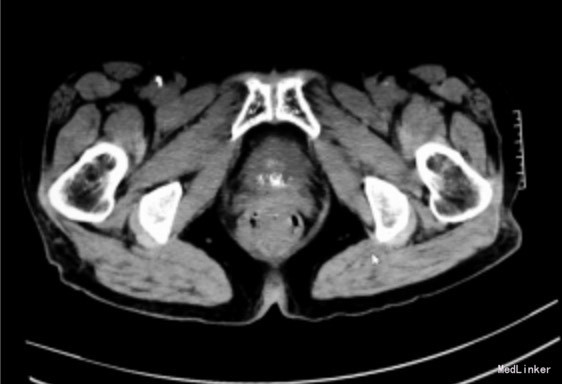

老年女性患者,70岁。主诉尿频、排尿费力、终末尿痛2个月

尿常规检查未见白细胞及红细胞,尿pH值7.3。CT检查示膀胱颈口有明显增厚及钙化灶(图1) 膀胱镜检查见膀胱三角区及颈口处黏膜明显增厚、隆起,表面糜烂并覆盖黄色细小颗粒状结石。取颈口及三角区组织行病理检查示:黏膜移行上皮增生,黏膜下大量钙盐沉积,少量炎细胞浸润,符合皮革性膀胱炎表现。

皮革性膀胱炎 治疗:蛛网膜下腔阻滞麻醉联合硬膜外麻醉下行经尿道膀胱三角区及颈口电切治疗,术中见黏膜层明显增厚、黏膜钙化明显,内含较多细结石,切至黏膜下层时结石消失。电切后观察无病变组织残留,三角区凹陷,正常黏膜下层裸露,部分区域可见肌层。

病理检查示膀胱黏膜慢性炎症、坏死,被覆上皮增生,固有层间可见钙盐沉着,纤维组织增生,较多中性粒细胞、嗜酸性粒细胞和淋巴细胞浸润。病理诊断:皮革性膀胱炎。 皮革性膀胱炎非常罕见,是一种较为严重的膀胱尿路上皮慢性炎症,可以导致膀胱黏膜水肿、糜烂和钙化斑块形成。本病大部分发生于年老体弱或免疫力低下者,是在特定的病理生理条件下形成的:①解脲棒杆菌感染,使尿液呈碱性,并致鸟粪石形成;②免疫功能低下;③泌尿系统有创检查或治疗致膀胱黏膜损伤、细菌污染。本病临床表现主要为尿痛、尿频、尿急、排尿困难等,有时伴有血尿,少数患者可有鸟粪石颗粒随尿排出或尿中有氨味。